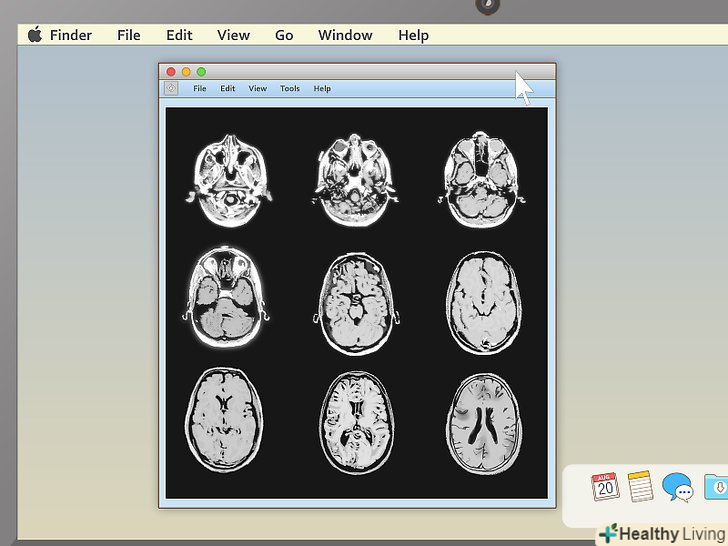

Перегляньте всі зображення.зазвичай в програмах для перегляду МРТ з одного боку екрану є велика чорна область, а з іншого - панель інструментів. Якщо ви бачите зображення попереднього перегляду в панелі інструментів, двічі клікніть по потрібному зображенню. Воно відкриється у великій чорній області.- Не поспішайте. Може здатися, що знімків мало, але насправді в кожному дослідженні міститься величезна кількість інформації, тому ваш комп'ютер може не відразу завантажити зображення.

Виберіть відповідний режим перегляду.програми для перегляду МРТ часто вміють показувати більше одного зображення за раз. Завдяки цьому лікарям простіше порівнювати різні проекції однієї і тієї ж області або навіть знімки, зроблені в різний час. Непрофесіоналові краще вибрати режим, при якому буде показуватися тільки одне зображення за раз, і переглядати знімки послідовно. Проте, в програмі повинна бути кнопка, що дозволяє показувати 2, 4 і більше знімків одночасно, тому не бійтеся її натискати.